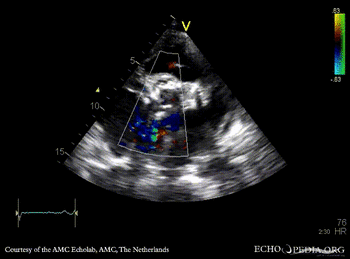

| PSAX: Color Doppler of aortic bioprosthesis